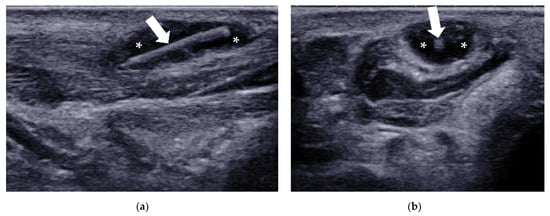

| Tenosynovitis | / | tendon sheath distension with surrounding effusion, “target” sign in transverse view |

| Adventitial bursitis | plantar side of the 1st and 5th metatarsal heads | unilocular area with heterogeneous echogenicity, compressible, with or without increased vascularity |